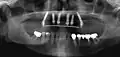

Implants en place. Notez qu'il y a moins d'implants que de dents sur la prothèse.

Prothèse totales fixes sur implants

Elles ont en règle réalisables sur six implants (selon des modalités bien précises pour l'observation desquelles le poseur d'implant doit avoir les qualifications requises). Selon la récession osseuse du patient à la suite de la perte de ses dents, on réalisera une prothèse sans ou avec fausse gencive. Moins coûteuses que les bridges, ces prothèses sont moins longues à réaliser. Rien n'empêche cependant le patient de faire remplacer sa prothèse résine par une prothèse céramique après une période d'observation de deux ans.